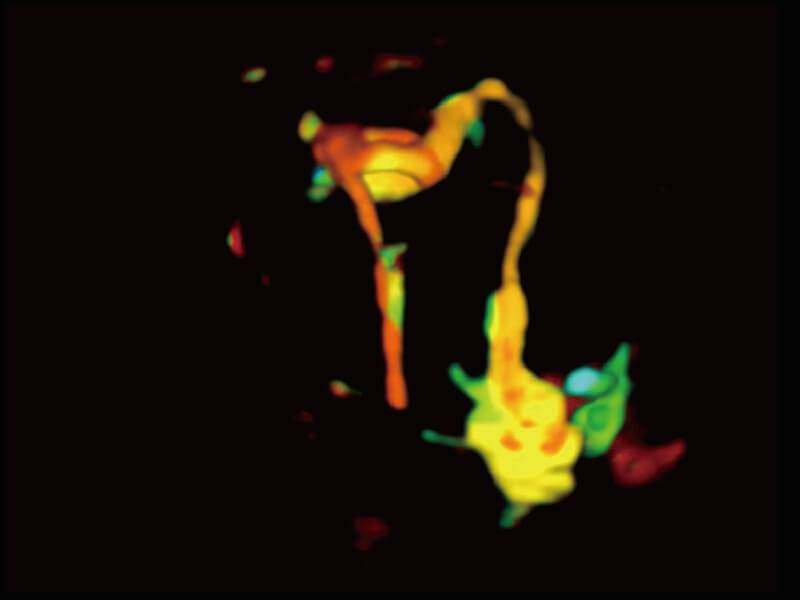

成像功能

S60探头工艺,从前端信号处理每一个环节采集无损声学数据,真实还原组织原貌,再现解剖细节。

超宽频带技术,为容积成像带来优质的二维图像基础,为您呈现丰富的结构细节,栩栩如生地展示宝宝的宫内形态以及各种组织的立体结构。